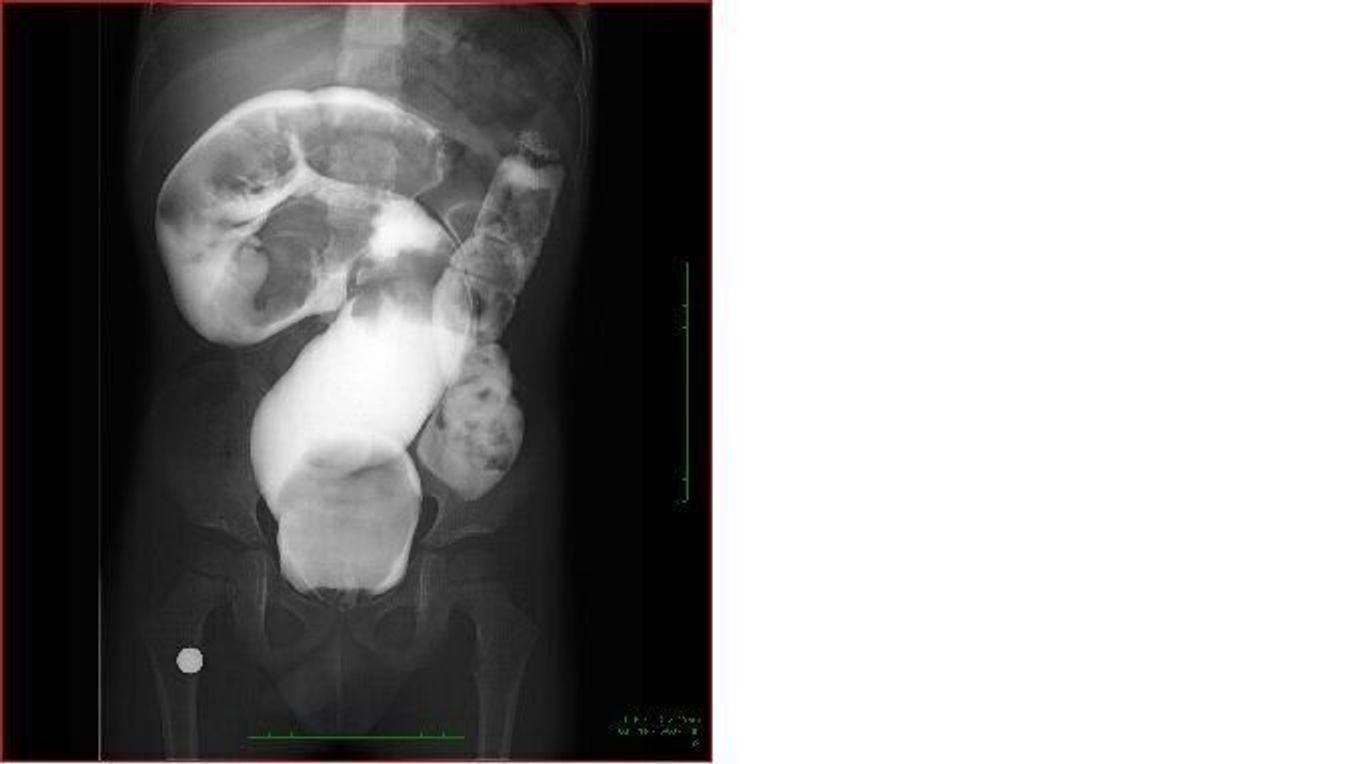

犬 便秘 レントゲン

動物病院の費用(猫の便秘)について 今日猫の便秘で動物病院に行ったら1万368円でした。この金額は妥当ですか。 内訳は 診察料 540円 レントゲン(2枚)43円 浣腸 16円 皮下点滴 1944円 皮下注射 1296円 内服薬(シロップ) 648円 でした。 猫のとらじ、1年半ぶりの便秘で通院中です。 今日撮ったレントゲンは、素人目にもお腹の中がウンチでギュウギュウでした。 今回の便秘の経過は、 10月8日に普通に排便 10月9,10日に便秘 レントゲン検査: 4000~8000円 (犬の大きさにもよる) 『バリウム造影検査』 レントゲンや超音波検査で胃や腸に 何らかの異常が見られる場合には より詳しく状態を見るための造影検査 が行われることもあります バリウム造影検査では 胃や腸管の

犬 便秘 レントゲンのギャラリー